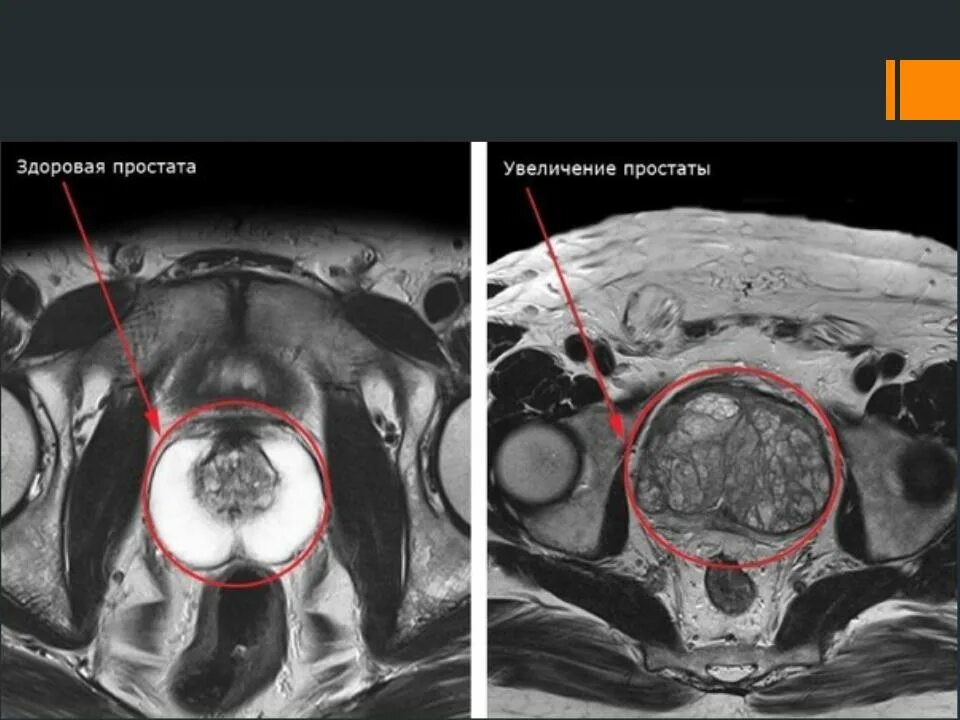

Адт при раке простаты